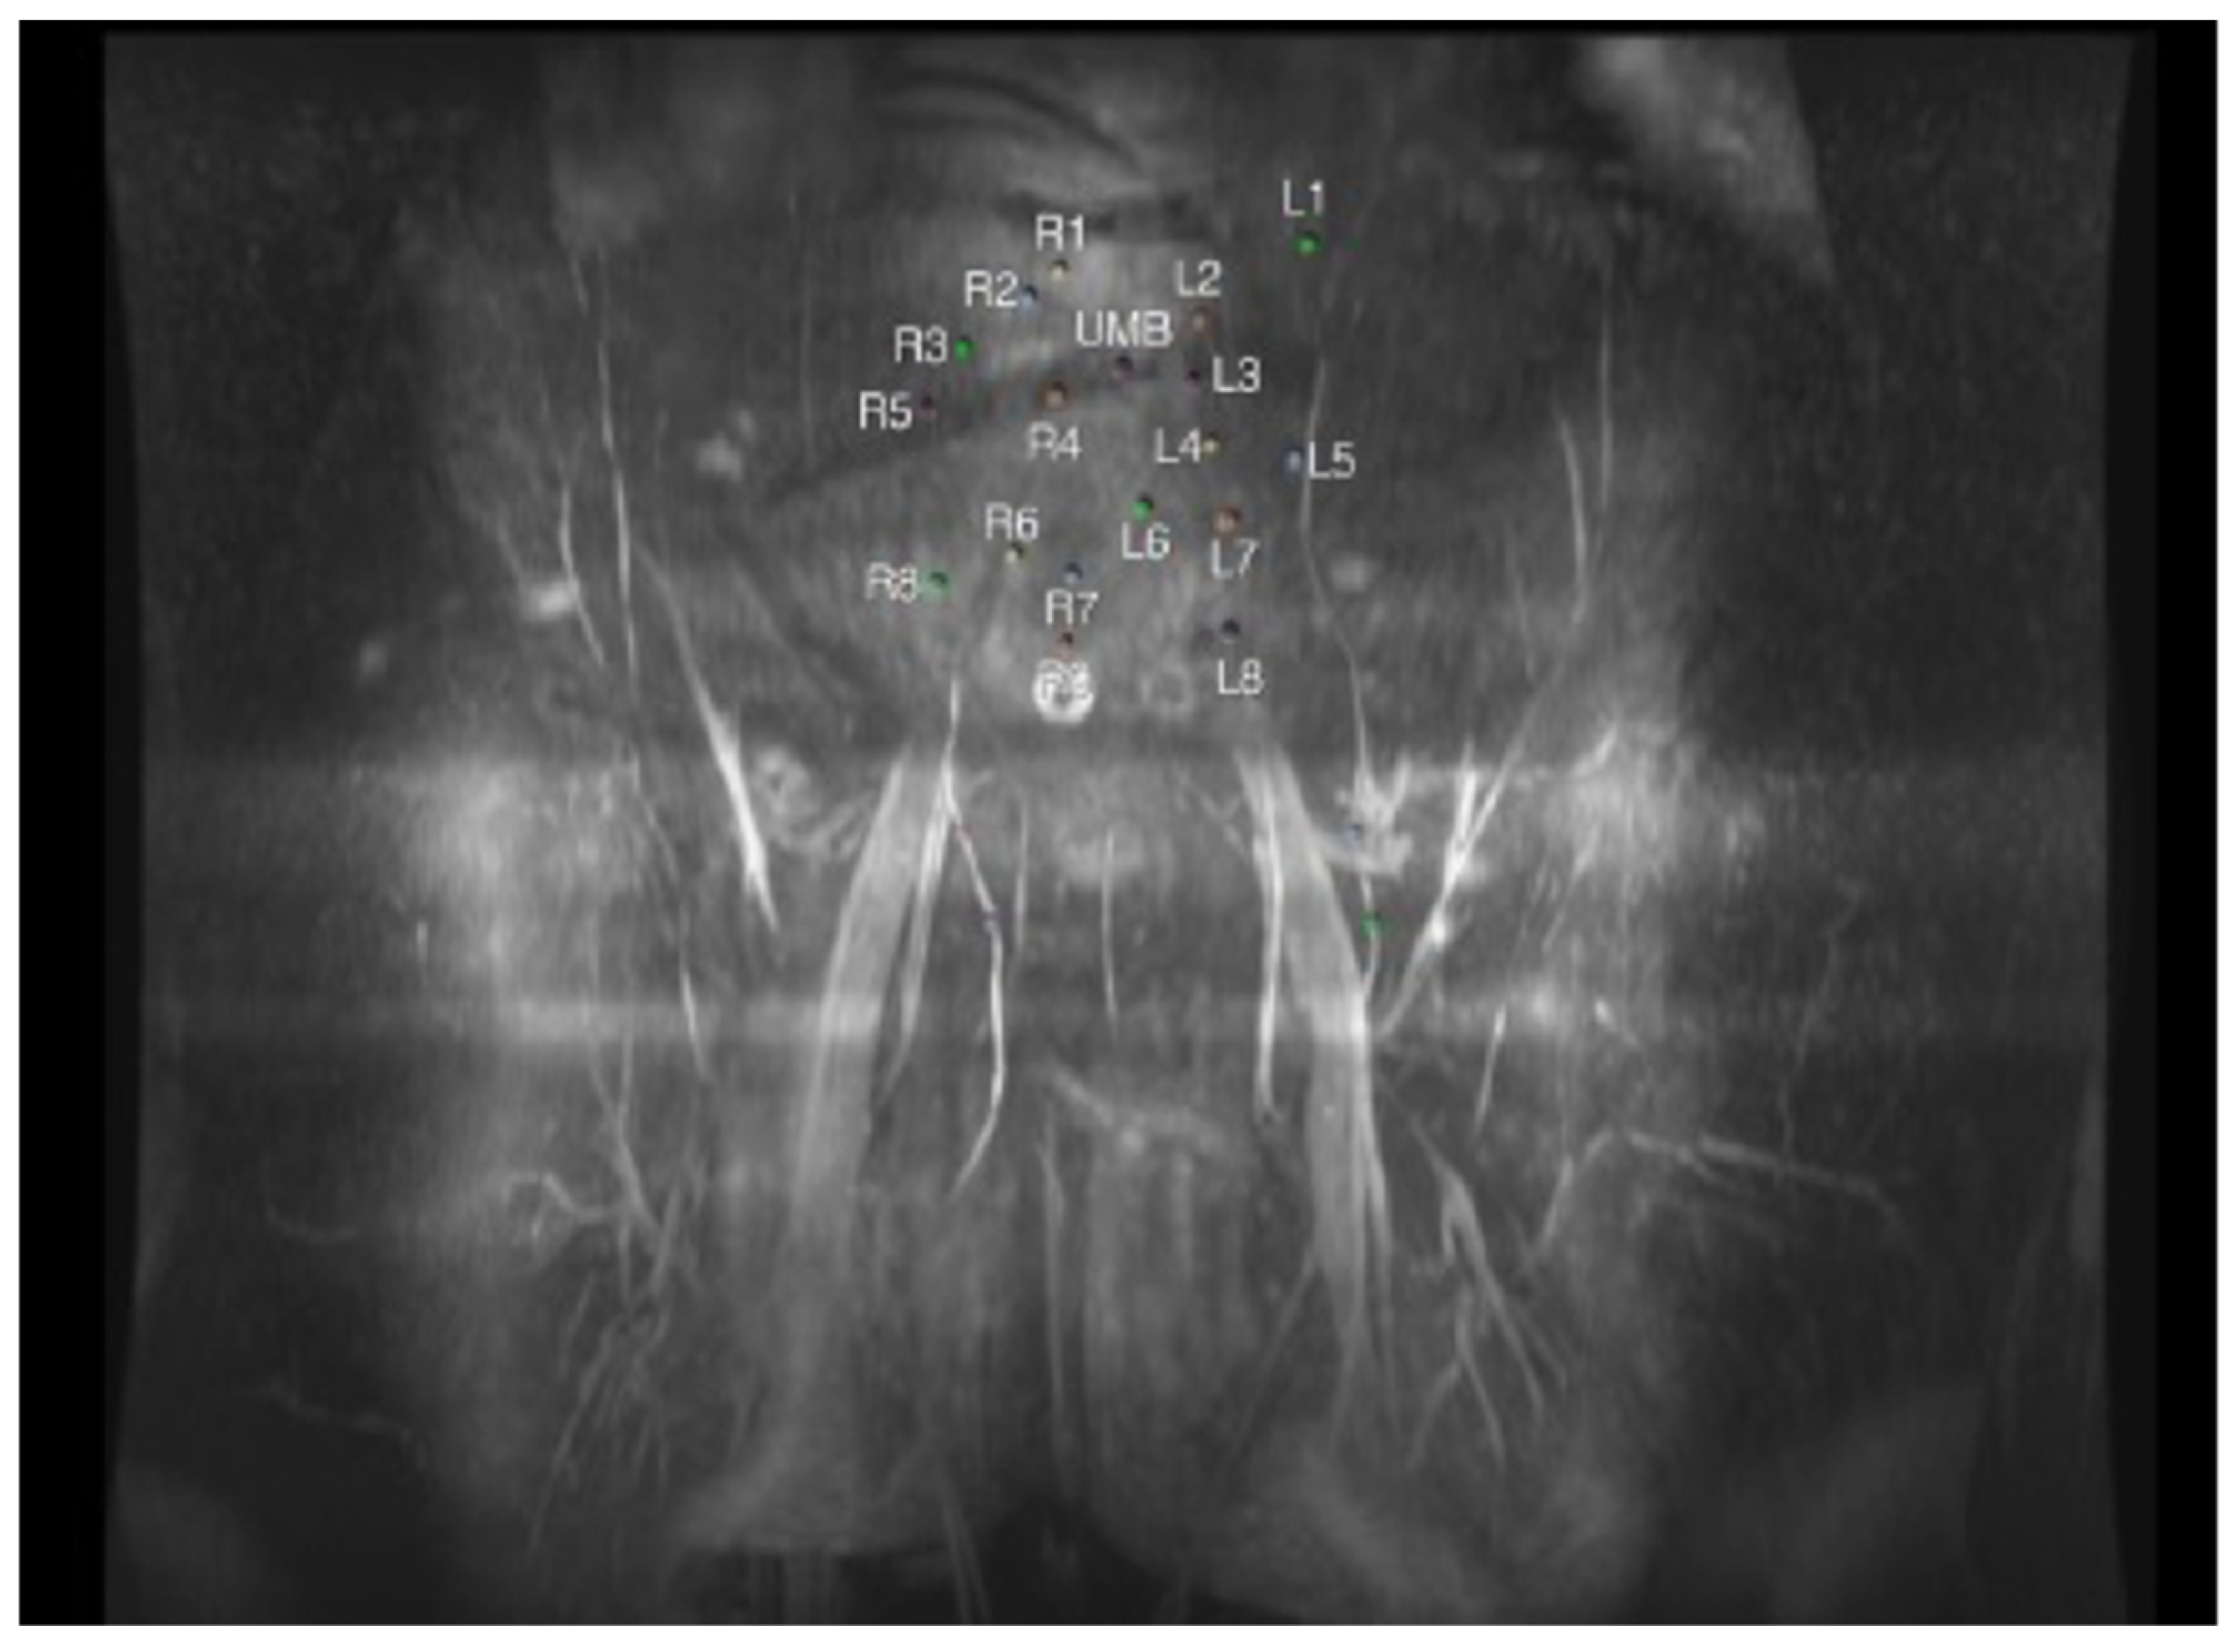

4. Magnetic Resonance Angiography (MRA)